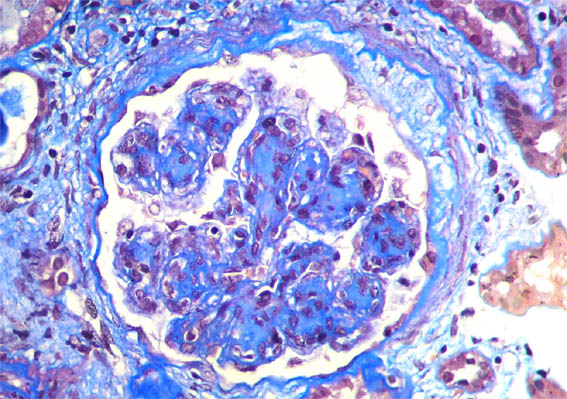

Figure 4.

Masson's

trichrome stain,

X400.